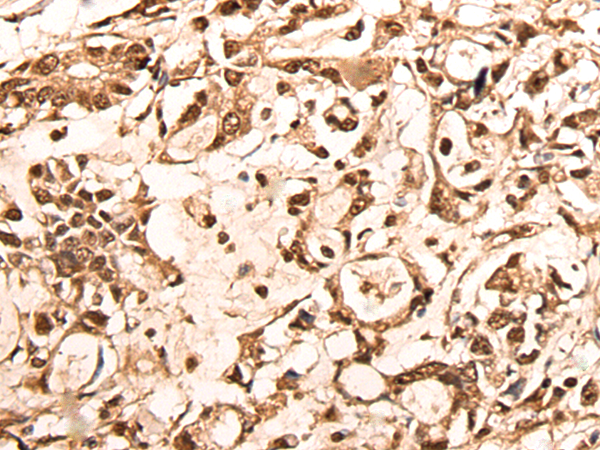

IHC positive control: |

Human ovarian cancer and human gastric cancer |

IHC Recommend dilution: |

25-100 |